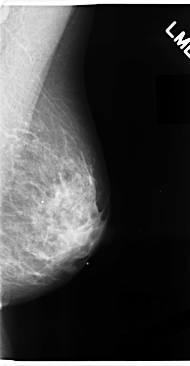

C_0077_1.LEFT_CC

LEFT_CC LINES 4736 PIXELS_PER_LINE 2536 BITS_PER_PIXEL 12 RESOLUTION 50 NON_OVERLAY